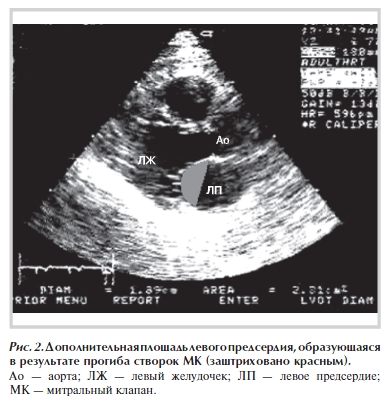

Площадь (S, см2) и дополнительный объем (V, мл) ЛП, образующиеся в результате прогиба створок МК в сторону верхушки ЛЖ в систолу, измеряли по длинной оси ЛЖ (рис. 2). Дополнительный объем ЛП оценивали по методу Симпсона. Расчитывали систолическую (Ss), диастолическую (Sd) площади митрального кольца, а также сократимость митрального кольца по формуле: C = [(Sd – Ss)/Sd] · 100%.

3. В остром периоде инфаркта миокарда происходят наиболее существенные изменения структур митрального клапана с последующей замедленной деформацией структур клапана в подострой стадии заболевания. Локальное изменение формы левого желудочка приводит к смещению папиллярных мышц от плоскости кольца митрального клапана, систолическому прогибу створок и точки

смыкания створок клапана в сторону верхушки левого желудочка с образованием регургитационного отверстия и дополнительного объема в левом предсердии.